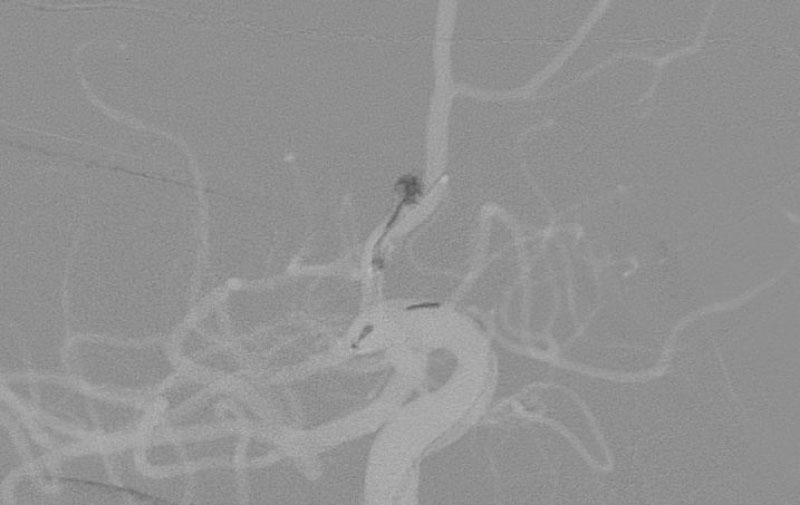

No.1627 手術中

No.1627 手術後